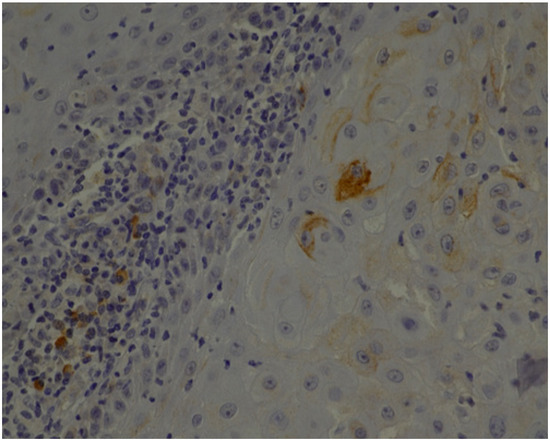

2.2. Histopathology and Immunohistochemistry

3.1. Histopathology and Immunohistochemistry